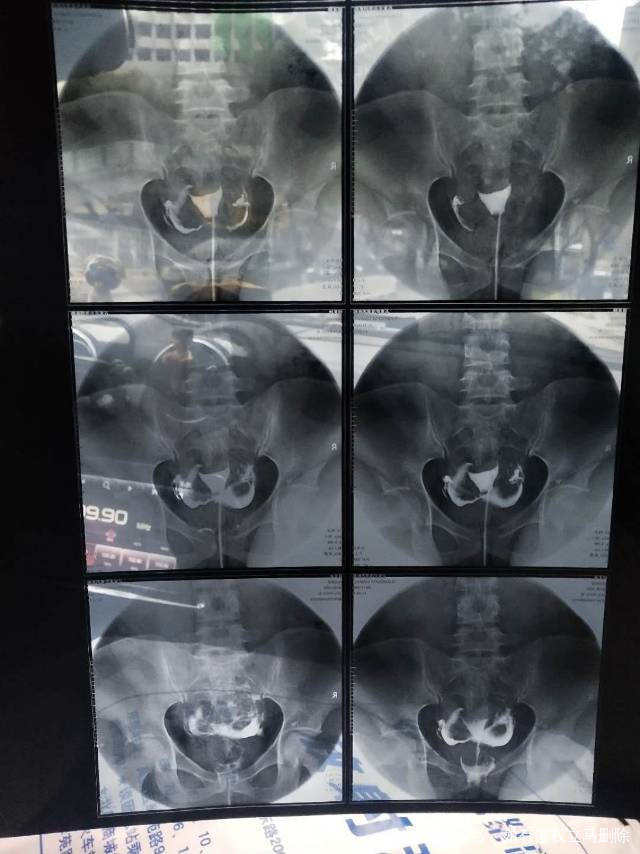

做完输卵管造影第六天了小腹还是感觉沉甸甸的如

可以热敷腹部,如果有发热,腹痛加剧,白带量多,有异味,随时就医